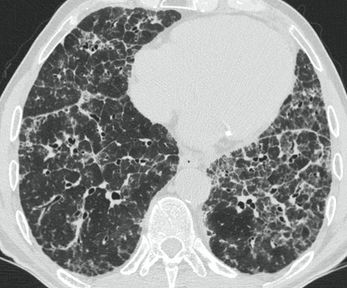

4.3. ЛУЧЕВАЯ ДИАГНОСТИКА COVID-19

Методы лучевой диагностики применяют для выявления COVID-19 пневмоний, их осложнений, дифференциальной диагностики с другими заболеваниями легких, а также для определения степени выраженности и динамики изменений, оценки эффективности проводимой терапии.

К методам лучевой диагностики патологии ОГК пациентов с предполагаемой/установленной COVID-19 пневмонией относят:

- Компьютерную томографию легких (КТ),

КТ имеет высокую чувствительность в выявлении изменений в легких, характерных для COVID-19. Применение КТ целесообразно для первичной оценки состояния ОГК у пациентов с тяжелыми прогрессирующими формами заболевания, а также для дифференциальной диагностики выявленных изменений и оценки динамики процесса. КТ позволяет выявить характерные изменения в легких у пациентов с COVID-19 еще до появления положительных лабораторных тестов на инфекцию с помощью МАНК. В то же время, КТ выявляет изменения легких у значительного числа пациентов с бессимптомной и легкой формами заболевания, которым не требуется госпитализация. Результаты КТ в этих случаях не влияют на тактику лечения и прогноз заболевания при наличии лабораторного подтверждения COVID-19. Поэтому массовое применение КТ для скрининга асимптомных и легких форм болезни не рекомендуется.

15. Рекомендации по формированию описаний и оценке изменений в легких и ОГК при имеющейся/подозреваемой пневмонии COVID-19 представлены в Приложении 1.